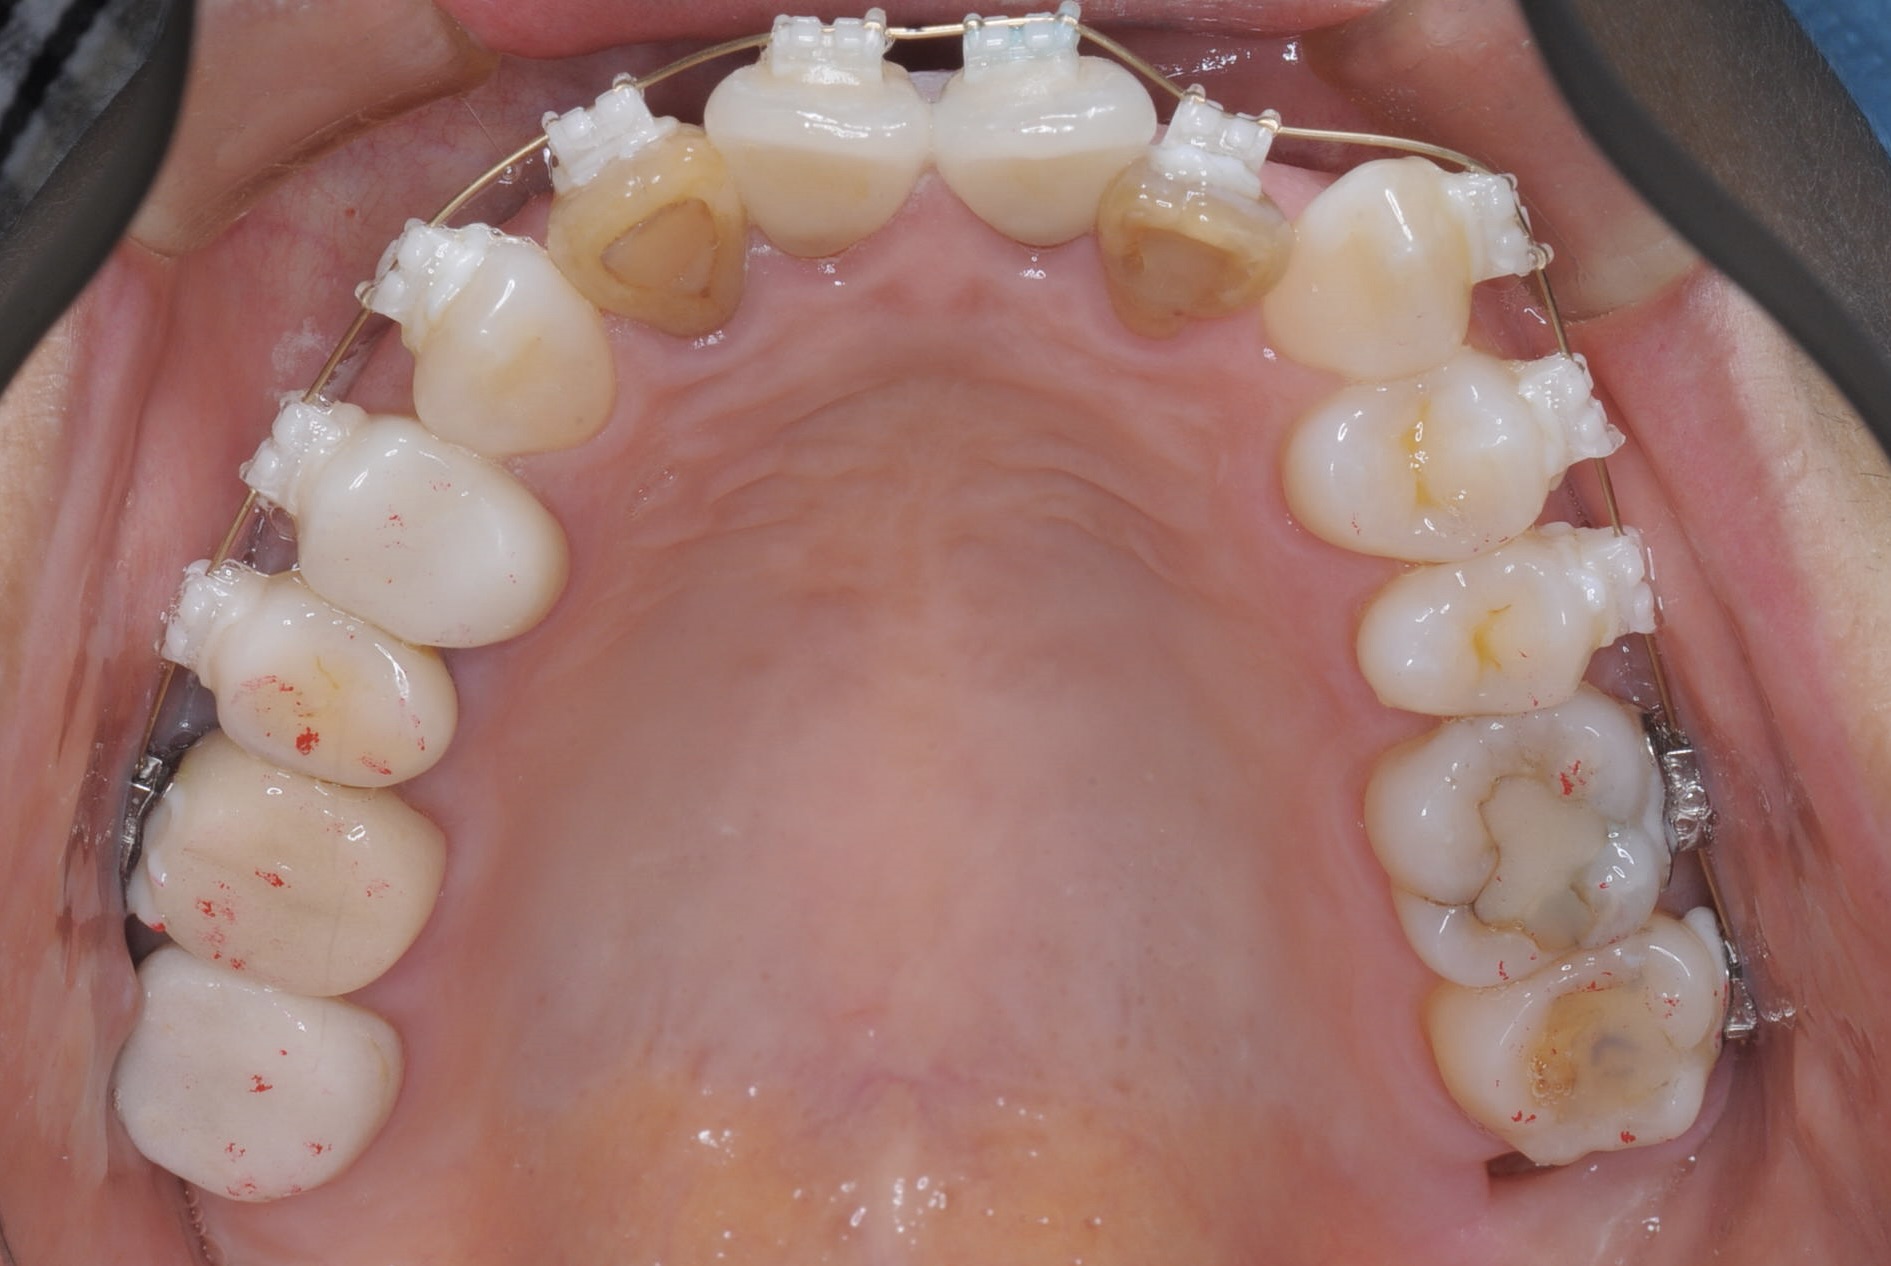

矯正治療スタート時(上顎)

メインテナンス時(上顎)